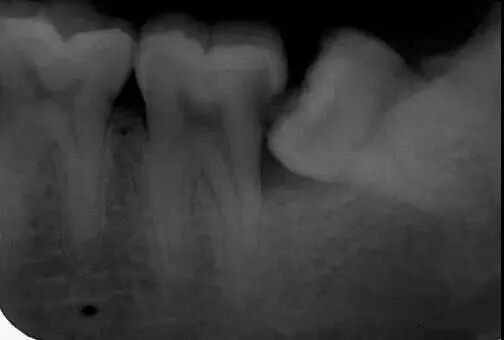

3、邻牙龋坏和牙周炎

智齿与邻牙之间有小的缝隙存在,食物残渣可以留存,长时间就可以导致邻牙发生龋坏和或牙周炎,如图所示: